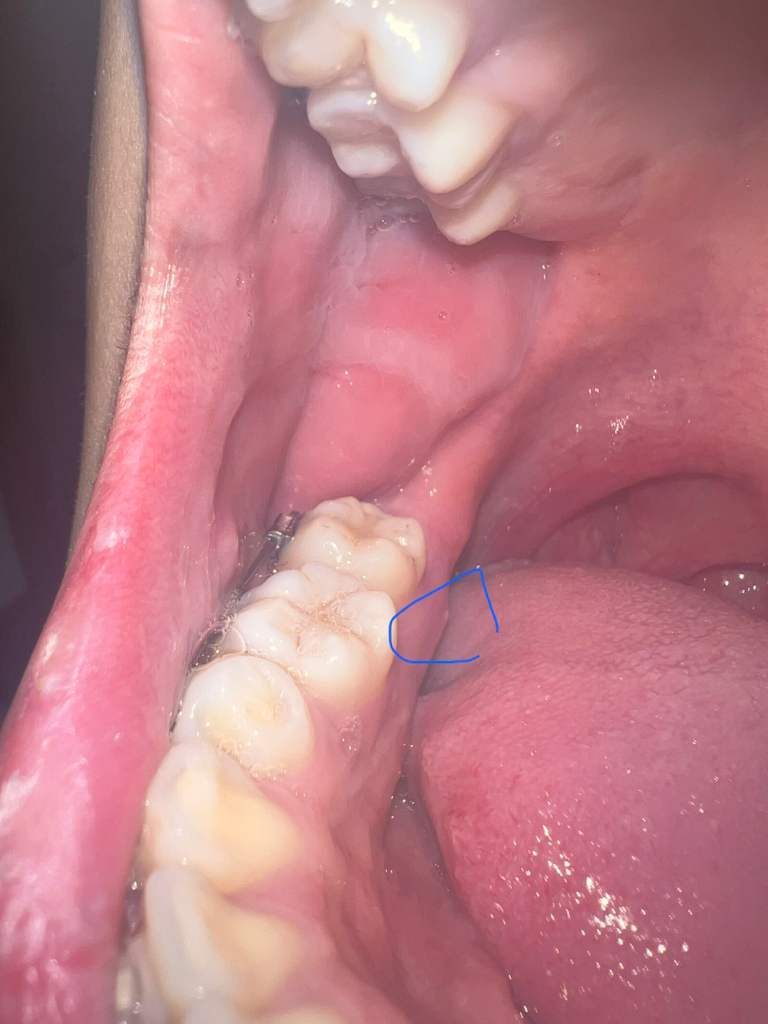

안녕하세요 한달전에 어금니 안쪽에서 이물감이 들더니 뭐가 튀어나와 찾아보니 뼈가 튀어나오는거라거 하더라구요 그러다가 한 2주전부터 슬슬 통증이 얼얼한? 묵직한 통증이 미미하게 있더라구요 ㅠ 밥먹을때나 찬물 뜨거운물엔 이상은 없는데 그냥 저기를 누르면 아파요 ㅠ 그러다가 흰색 튀어나온 부분에서 고름같은게 나와서 너무 당황스러워서 치과에 방문해서 진찰을 받으니 뼈가 튀어나온게 맞다고 하더라구요 ㅠ 그리고 치근단 엑스레이도 촬영해서 치아쪽 이상이 아니라 잇몸 궤양이 일어난거같다고 항생제랑 소염진통제 5일치 처방해줬어요.. 약먹고나서 3일정도 됐는데 고름은 이제 눌러도 안나오는데 통증은 뭔가 그대로인 느낌이에요 혀나 손으로 누르면 통증이 있어요 ㅠㅠ 턱관절에도 이상이 있는거같긴한데.. 확실히 여기 이 튀어나온 부분을 누르면 통증이 있는건 맞는거같아요 ㅠ 혹시 이거 큰병인지 너무 걱정되서 글 써봅니다 의견 부탁드립니다 선생님들!